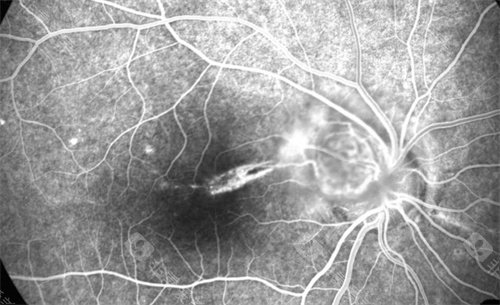

在探讨眼科疾病治疗时,眼底病的治疗备受关注,而武汉协和医院在这方面的表现值得深入了解。

在眼底病治疗方面,医生们能够运用可靠的技术和丰富的经验,为患者制定个性化的治疗方案。